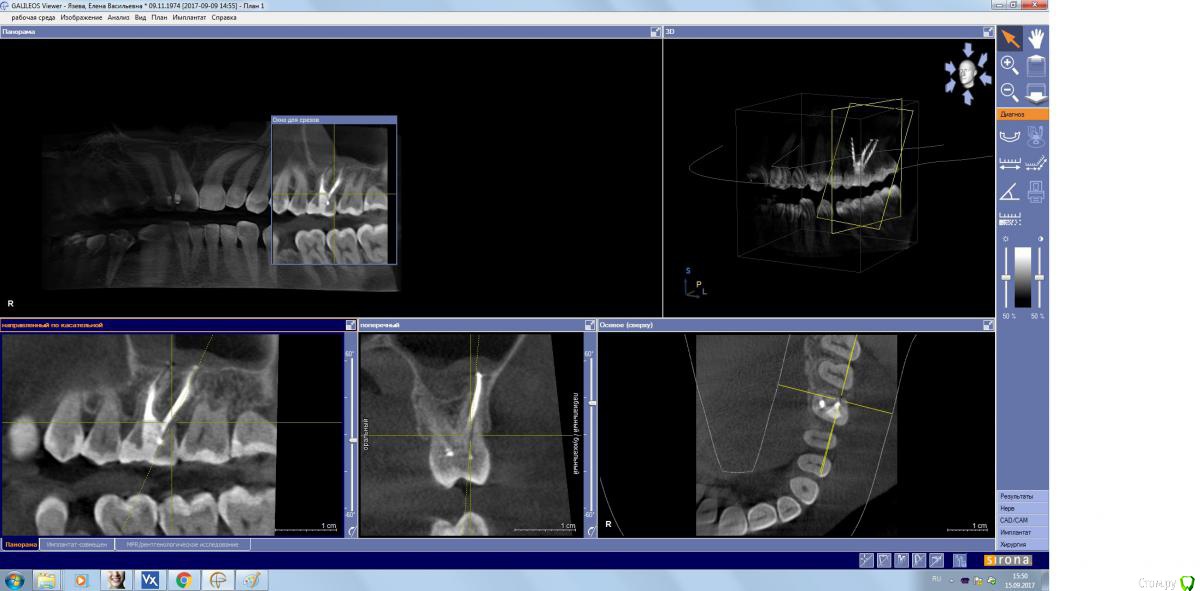

kamranchick Опубликовано 15 сентября, 2017 Поделиться Опубликовано 15 сентября, 2017 Господа, терапевт наш пролечил зуб, и болит пазуха уже месяц... сам зуб не болит, какой план действий? Ссылка на комментарий

kamranchick Опубликовано 15 сентября, 2017 Автор Поделиться Опубликовано 15 сентября, 2017 (изменено) Лор говорит хронический гайморит в стадии обострения, но провоцирует зуб, короче все как всегда... Изменено 15 сентября, 2017 пользователем kamranchick Ссылка на комментарий

kamranchick Опубликовано 15 сентября, 2017 Автор Поделиться Опубликовано 15 сентября, 2017 хотя бы узнать, это по нашей части, вернее мы виноваты или это со стороны лор что то, куда пациента определять... или опять в зуб лезть Ссылка на комментарий

parallax Опубликовано 16 сентября, 2017 Поделиться Опубликовано 16 сентября, 2017 Это пристеночно-гиперпластическая форма гайморита, застарелая хронь, которая появилась не вчера. Возможно, обострение спровоцировали паффы (куда ж без них). Я думаю, стоматологи тут не при чём. Хотя ЛОРики всегда обвиняют нас (скоро вменят убийство Кеннеди). В каналы лезть больше не надо, отправляйте в ЛОР отделение, лечение этого гайморита хирургическое. 1 Ссылка на комментарий

ger_berra Опубликовано 2 октября, 2017 Поделиться Опубликовано 2 октября, 2017 Решётчатый лабиринт посмотрите. Там часто много чертей сидит. Ссылка на комментарий